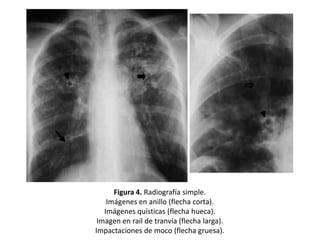

Figura 4. Radiografía simple.

Imágenes en anillo (flecha corta).

Imágenes quísticas (flecha hueca).

Imagen en rail de tranvía (flecha larga).

Impactaciones de moco (flecha gruesa).

Signos radiológicos

sin nivel hidroaéreo. (Figuras 2 y 4)

• Opacidades tubulares u ovoides (impactos

mucoides) que corresponden a bronquios

repletos de moco o líquido.

• En algunas ocasiones los bronquios, llenos de

secreciones, pueden visualizarse como

imágenes lineales densas en forma de Y, de V

o en dedo de guante. (Figuras 4 y 5)